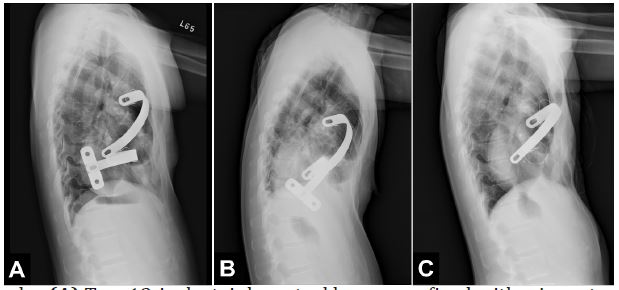

A 43-year-old woman presented with occasional chest discomfort since adolescence. She came to the outpatient clinic for medical consultation, where pectus excavatum was diagnosed (Haller index of 7.5 and sternovertebral distance of 6.2 cm), and the Nuss procedure was arranged by a thoracic surgeon. She had no known past medical history, and the cardiac workup did not reveal dysrhythmias or any structural abnormalities, including intracardiac thrombi. During the operation, two stainless steel bars were inserted and fixed with wire sutures, leaving the lower stabilizer (Figure 1A). Her postoperative clinical course was uneventful, so she was discharged on the eighth day after the surgery.

Two months later, her palpitations did not improve, and she also experienced chest discomfort, back pain, dyspnea, and even symptoms of heart failure. Under the suspicion of pectus bar displacement, she was hospitalized, and lower Nuss bar flipping was confirmed (Figure 1B). The patient was then referred for metal bar removal surgery. The operation was performed under general anesthesia, and hemorrhage from the surgical wound was noticed after removing the bars and wires. Because cardiac perforation was highly suspected, TEE examination was ordered. It revealed an intact cardiac surface, but a floating Right Atrial (RA) thrombus extending to the Right Ventricle (RV) and Right Ventricular Outflow Tract (RVOT) with moderate Tricuspid Regurgitation (TR) was incidentally found (Figures 2 and 3). Anticoagulant therapy with low-molecular-weight heparin was given postoperatively in the Surgical Intensive Care Unit (SICU). Coagulation workup did not reveal a hypercoagulable state. Computed tomography angiography did not find pulmonary embolism, and deep venous thrombosis was also excluded by compression ultrasound examination on deep veins of bilateral lower extremities. Because RHT remained a potential risk for serious thromboembolic events and needed to be addressed accordingly, further surgical management with open thrombectomy was scheduled three days after the last surgery.

During the operation, a severe band-like adhesion around the pericardial space was noticed, which resulted in a local constriction of the right heart [3]. Cardiotomy was performed following the initiation of cardiopulmonary bypass. On inspection, there was a large RA thrombus extending to the Tricuspid valve (TV), RV and RVOT, which was organized and easily fragmented and had broad-based attachments to the RA and RV free walls. After thrombectomy, TV perforation and RA defects were found, and TV replacement and bovine pericardial patch reconstruction were performed. Afterward, modified reconstruction of pectus excavatum, i.e., combined Ravitch and Nuss procedures, was performed by the thoracic surgeon (Figure 1C). The patient was then transferred to the SICU after the surgery. Her postoperative course was uneventful, and she was discharged one week after the last surgery.

Figure 1: Lateral chest radiographs. (A) Two 13-inch stainless steel bars were fixed with wire sutures and left lower stabilizer on the first postoperative day. (B) Obvious upward flipping of the lower metal bar one month after the Nuss procedure. (C) Image after surgical thrombectomy, combined Ravitch and Nuss procedure with one supporting bar for pectus excavatum reconstruction, and tricuspid valve replacement.